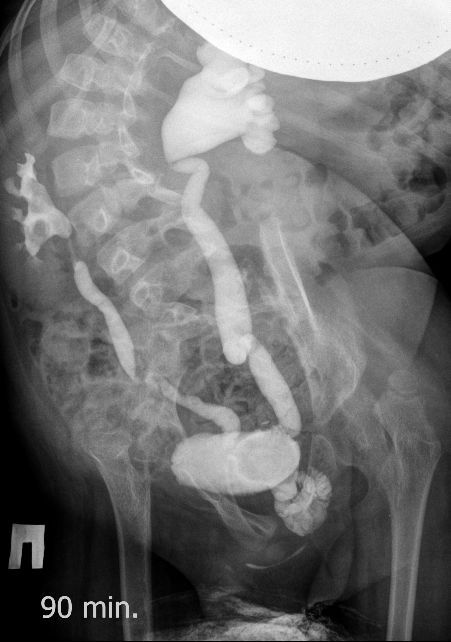

Поскольку откликов нет, добавляю экскреторные урограммы этого же пациента

DX0001.jpg

DX0002.jpg

DX0003.jpg

DX0004.jpg

DX0005.jpg

Нейрогенный мочевой пузырь (?), МКБ, конкремент мочевого пузыря, двухсторонний мегауретер, конкремент правой почки.